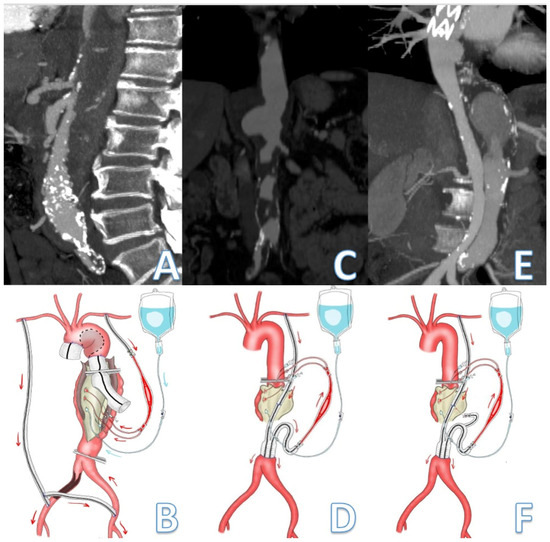

Figure 2. Schematic representation passive shunt according to the extension of the thoracoabdominal aortic aneurysm. Visceral and lower limb perfusion is assured by the passive shunt while Custodiol solution is used for renal arteries perfusion. A patient presenting with a type II dissecting TAAA. (A,B) Preexisting axillo-bifemoral bypass was used to perfuse the lower limbs while a second graft anastomosed to the LSA provided flow to the visceral vessels. (C,D) A PS between the LSA and the infrarenal aorta was created using a reversed bifurcated 8 mm Dacron graft for visceral perfusion during treatment of a type III TAAA. (E,F) A PS between the LSA and infrarenal aorta assure revascularization of CT, SMA, and intercostal artery during surgical repair of a type II-dissecting TAAA in a patient who has previously undergone TEVAR. The arrows indicate the direction of the blood flow from the inflow vessel to assure visceral perfusion during aortic cross-clamping.